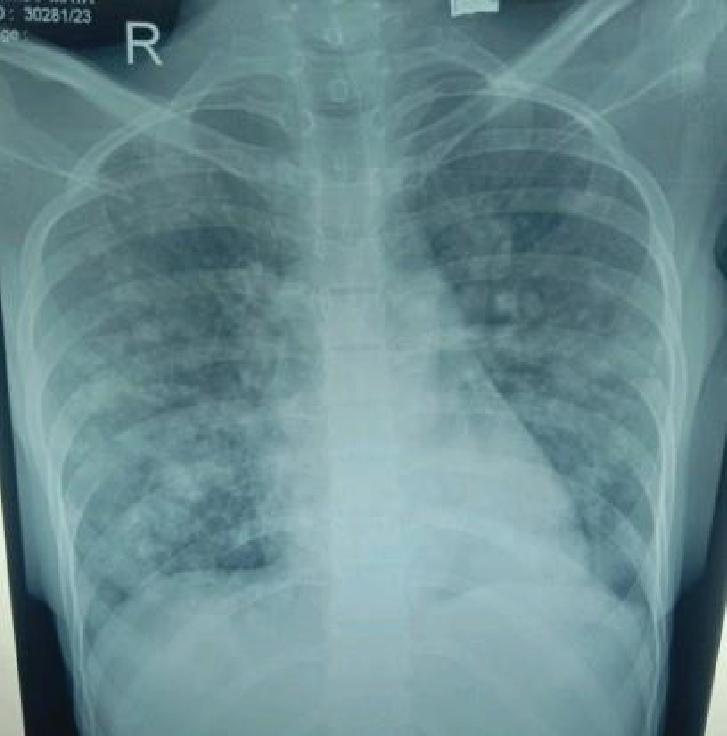

NCCT head revealed new subarachnoid hemorrhage (SAH) in left parietal lobe region with old intracerebral hemorrhage (ICH) changes (Fig. 3). Routine investigations were sent including CBC, LFT, RFT, thyroid profile. Chest X-ray showed multiple heterogeneous opacities in bilateral lung fields (Fig. 4). Bedside USG abdomen and pelvis showed heterogeneously enlarged uterus with echogenic mass seen in pelvis and bilateral adnexa are not visualized separately. There was also mild right-sided hydroureteronephrosis. Other investigations like serum vitamin B12, human immunodeficiency virus (HIV) enzyme-linked immunosorbent assay (ELISA); sputum for culture, acid fast bacilli (AFB), CBNAAT; ANA, cytoplasmic- antineutrophil cytoplasmic antibodies (cANCA), perinuclear-ANCA, antiphospholipid antibodies (APLA), coagulation profile, peripheral blood smear (PBS) were sent. The results are shown in Table 1.

Figure 4. Chest X-ray PA view showing nodular opacities in bilateral lung fields suggestive of metastatic lesion.